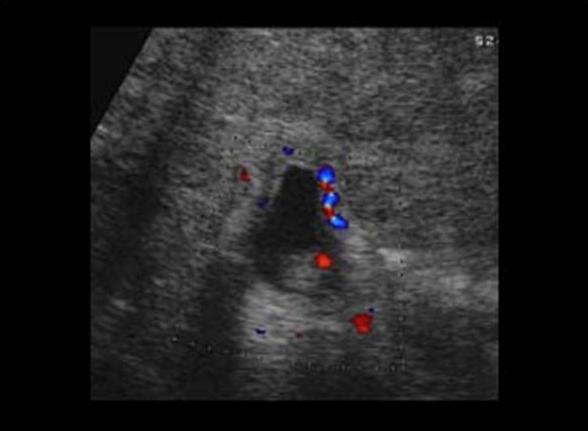

Mirizzi SYndrome

impacted stone in the cystic duct or GB neck

presence of two tubular structures representing the bile duct above the level of the cystic duct

Mirizzi SYndrome

impacted stone in the cystic duct or GB neck

presence of two tubular structures representing the bile duct above the level of the cystic duct